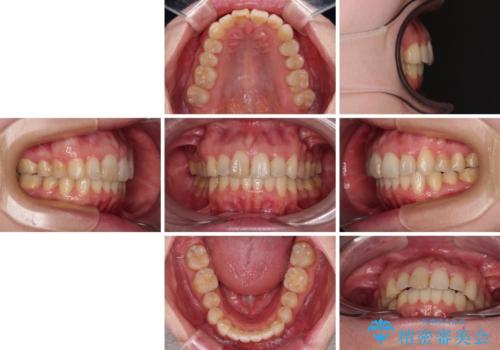

カリエール・ディスタライザーを用いたことで上顎前歯の突出感はスムーズに解消され、歯列不正は1年半ほどでほぼ改善することができました。

しかし、その後インビザライン特有の奥歯がうまく噛めないという問題が長引き、改善に1年近い期間を要することとなりました。